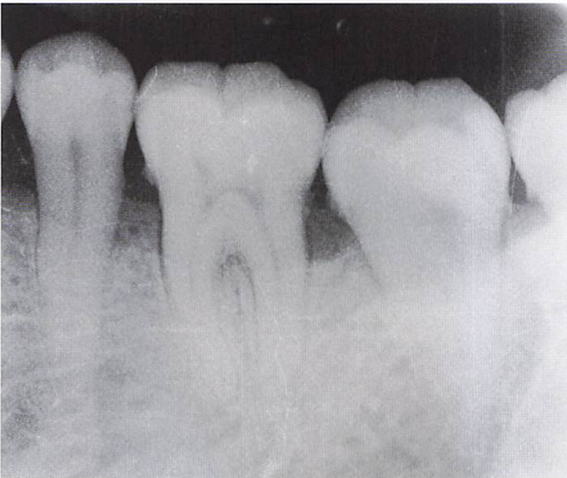

午前-43

32歳の男性。歯ぐきからの出血と排膿が続くようになったことを主訴として来院した。数年前から歯の動揺が気になっていたという。22歳から毎日10本の喫煙をしているが、 全身的な疾患はない。歯周基本治療時の口腔内写真と初診時のエックス親画像を別に示す。 この疾患の特徴はどれか。2つ選べ。

a.栄養障害が原因である。

b.家族内集積が認められる。

c.歯槽骨の破壊が急速である。

d.辺縁歯肉の壊死と潰瘍を認める。

b.c